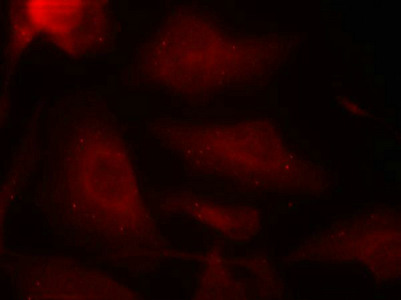

Immunofluorescence staining of methanol-fixed Hela cells using Tau(Phospho-Ser404) Antibody.